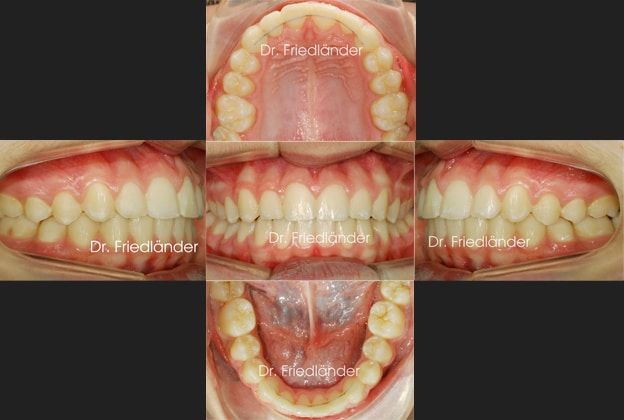

Una vez haya acabado el recambio dental se colocaron brackets mediante cementado directo en los demás dientes y se continuó con el tratamiento.

Detalle de la boca después de retirar los aparatos 22 meses después.

Comparación del antes y el después